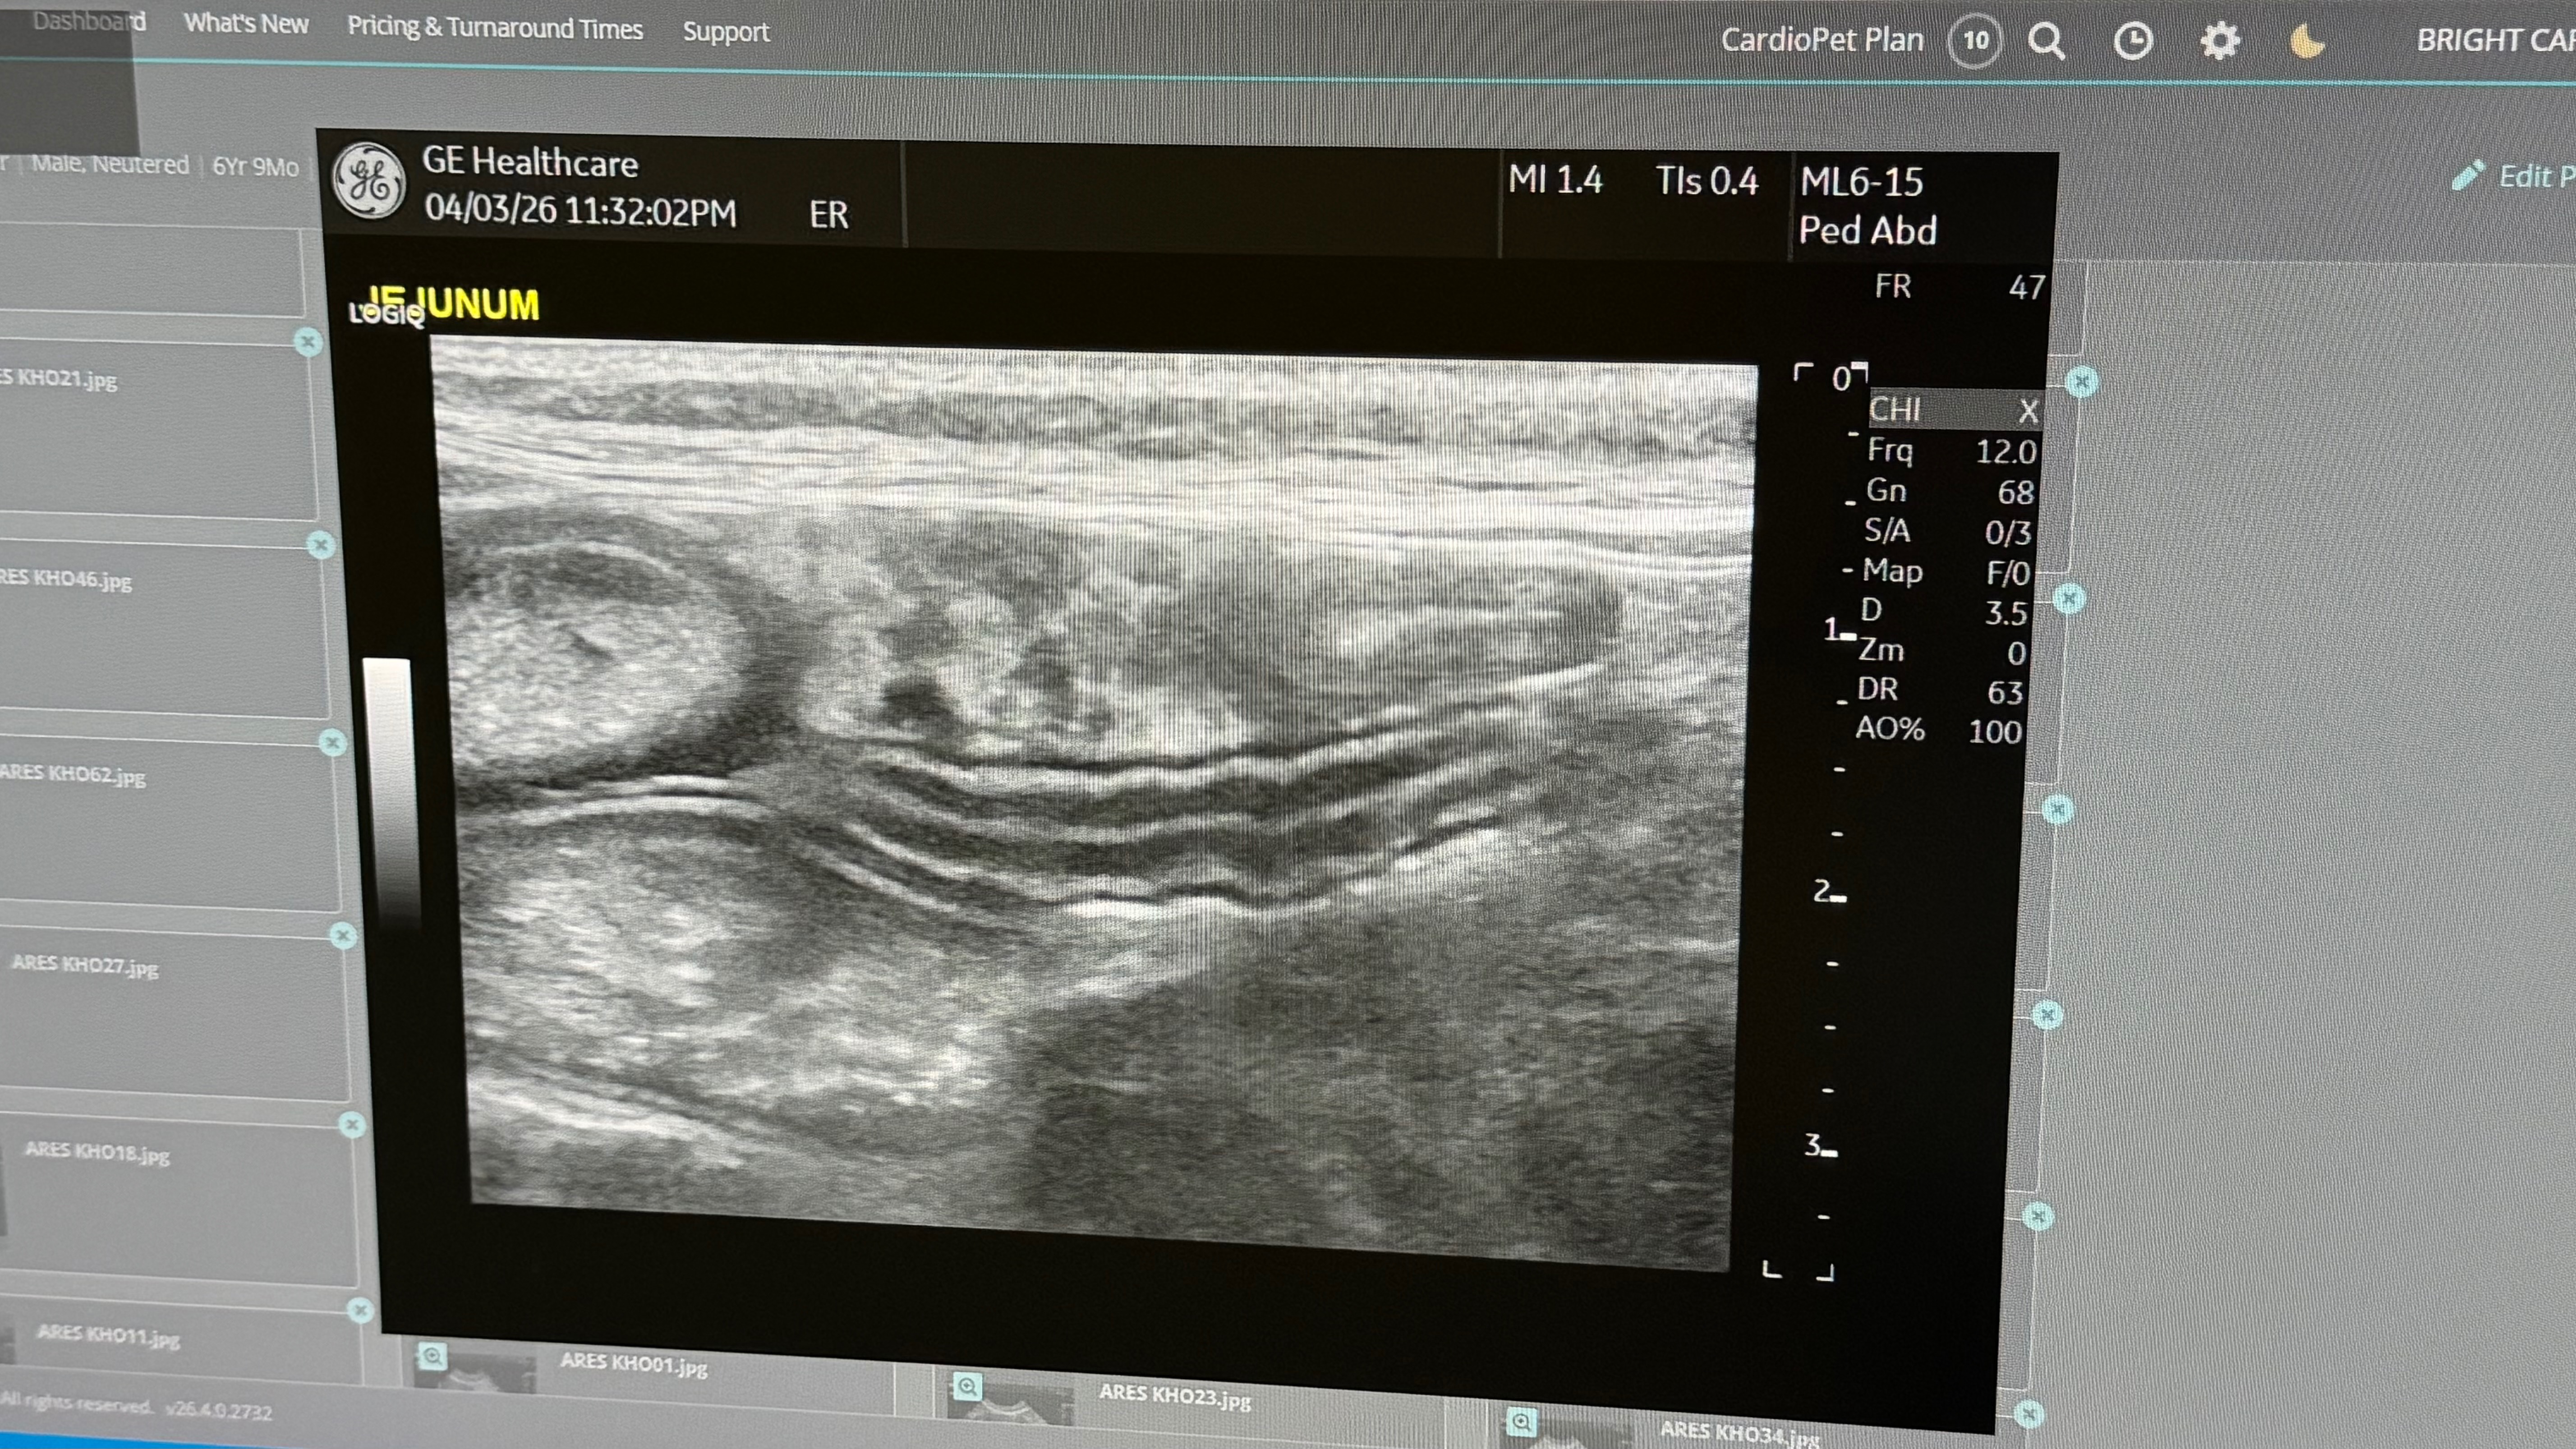

Recently, Ares started experiencing serious medical issues. His very first vet misdiagnosed him as prediabetic without doing the proper blood work. As his symptoms got worse, I sought a second opinion. After multiple ultrasounds and a sample sent to a cytologist, we learned that Ares most likely has irritable bowel disease. Unfortunately, things didn’t stop there. Ares continued to decline and was hospitalized for a week at CASE Hospital, fighting off a lung and kidney infection. While those areas improved, the doctors discovered his intestines were inflamed and he had a GI issue. After many assessments, they found a mass that’s blocking 90% of his intestines, and it’s most likely GI Lymphoma.